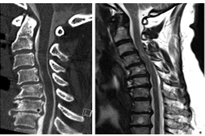

Ein zentraler Schwerpunkt unserer Forschung liegt auf der Pathophysiologie und Biomarkerentwicklung bei der degenerativen zervikalen Myelopathie (DCM). Dabei untersuchen wir insbesondere die Rolle der Blut-Rückenmark-Schranke (BSCB), deren präoperative Störung mit dem klinischen Schweregrad sowie dem postoperativen neurologischen Outcome assoziiert ist und sich nach chirurgischer Dekompression teilweise erholt. Aktuell prüfen wir, inwieweit die BSCB-Störung als verlässlicher Prädiktor für den Krankheitsverlauf dienen kann und ob Zusammenhänge mit elektrophysiologischen Veränderungen bestehen.